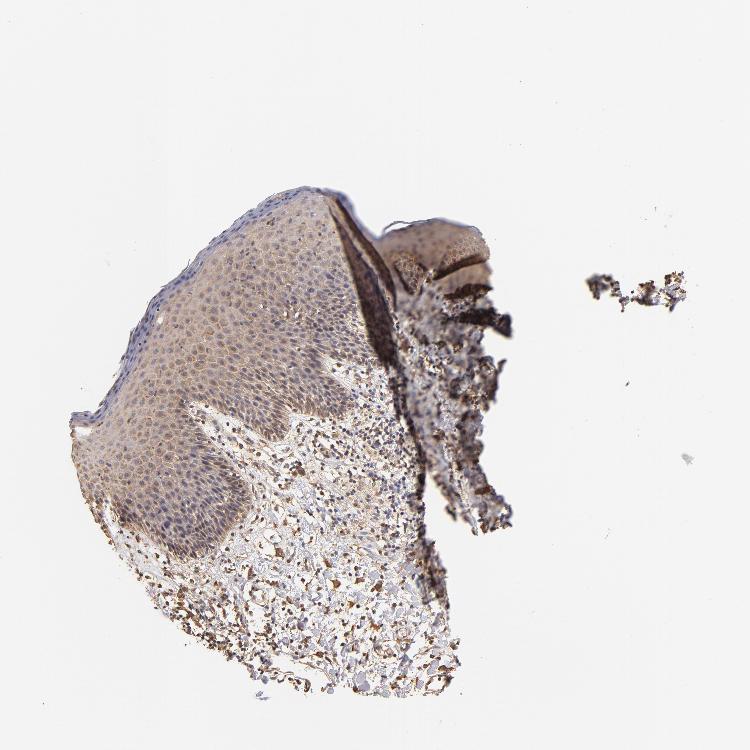

SKIN 1 - Antibody stainingi

Antibody staining in the annotated cell types in the current human tissue is reported as not detected, low, medium, or high, based on conventional immunohistochemistry profiling in selected tissues. This score is based on the combination of the staining intensity and fraction of stained cells.

Each image is clickable and will lead to virtual microscopy that enables deeper exploration of all samples and also displays staining intensity scores, fraction scores and subcellular localization as well as patient and tissue information for each sample.

Antibody HPA003910

Langerhans Not detected

Fibroblasts Not detected

Keratinocytes Not detected

Melanocytes Not detected

SKIN 2 - Antibody stainingi

Epidermal cells Medium